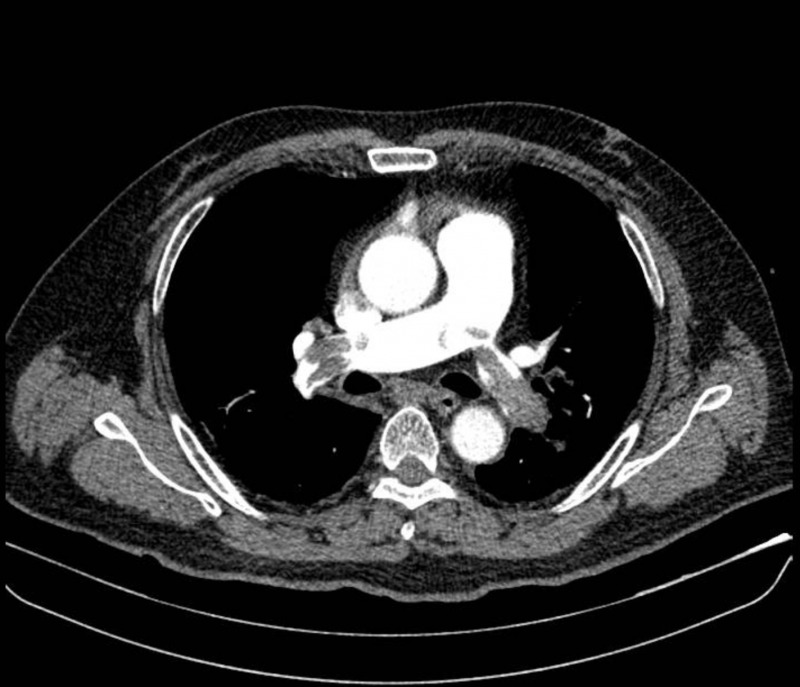

Ông N.V.L (51 tuổi, ngụ tại Tây Ninh) được đưa vào Bệnh viện Nhân dân 115 (TP.HCM) trong tình trạng khó thở, mạch nhanh, huyết áp khó đo sau khi bất ngờ ngất xỉu khi đang làm việc ngoài đồng.

Trước đó, ông xuất hiện các triệu chứng như chóng mặt, nặng ngực.

Tại tuyến đầu, ông được chẩn đoán nghi nhồi máu cơ tim và nhanh chóng chuyển viện. Kết quả chụp CT mạch máu phổi tại Bệnh viện Nhân dân 115 cho thấy ông bị thuyên tắc phổi cấp, huyết khối lớn bít tắc hai bên động mạch phổi, gây sốc tắc nghẽn. Bệnh nhân được điều trị bằng thuốc tiêu sợi huyết, hồi phục sau một tuần.

Siêu âm mạch chi dưới phát hiện huyết khối ở tĩnh mạch đùi và khoeo chân trái. Các bác sỹ xác định nguyên nhân có liên quan đến thói quen hút thuốc lá hơn 20 năm của bệnh nhân, với mức độ hút khoảng một gói mỗi ngày.